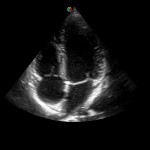

Whilst transoesophageal echocardiography (TOE or TEE) remains the gold standard for investigating many cardiac shunts, a large number of defects can be detected using standard transthoracic echocardiography (TTE), particularly when employing microbubbles as contrast agents. Certainly, remodeling (dilatation, hypertrophy) secondary to a long-standing shunt is immediately obvious.